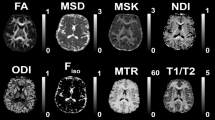

Current advances in MRI physics allow for neurobiological characterisation of brain tissue properties based on biophysical models20. The neurite orientation dispersion and density imaging (NODDI) model using diffusion-weighted imaging (DWI) data provides markers of axonal density and unbound tissue water content along with an estimate of fibre orientation dispersion21. Relaxometry-based measures of magnetization transfer saturation (MTsat) are indicative of fibre myelination and are therefore complementary to DWI-based measures (for review see ref. 22).

On diffusion-weighted MR images, we applied TractSeg25—an automated deep-learning-based method —to segment the WM of each individual into 31 tracts-of-interest composed of 14 association tracts, 4 projection tracts, 6 limbic tracts and 7 segments of the corpus callosum (see Fig. 1 and Methods for details). We then sampled and averaged MRI-derived maps indicative of myelin content (MTsat), axonal density (intra-cellular volume fraction; ICVF), free water (isotropic volume fraction; ISOVF) and tract volume (number of voxels). Mean and standard deviation values for each tract are shown in Supplementary Data 1. In the following sections, we use interchangeably MRI indices names (MTsat, ICVF, ISOVF) and the brain tissue properties they are indicative of (myelin, axonal density, free water) according to the underlying biophysical model20, aiming to facilitate reading. We acknowledge that the present results refer to MRI maps which are neither direct nor perfect measures of underlying histological tissue properties.

We acquired MRI data on a 3 T whole‐body system (Magnetom Prisma - Siemens, Erlangen - Germany), with a 64-channel radiofrequency receive head coil and body coil for transmission. The quantitative MRI protocol included three multi-echo 3D fast low angle shot (FLASH) acquisitions with magnetization transfer-weighted (MTw: TR = 24.5 ms, α = 6°), proton density-weighted (PDw: TR = 24.5 ms, α = 6°) and T1-weighted (T1w: TR = 24.5 ms, α = 21°) contrasts with 1 mm isotropic resolution24,43,78. We used B1 maps computed with the 3D echo-planar spin-echo and stimulated echo images79,80 (4 mm resolution, TE = 39.06 ms, TR = 500 ms) to correct for the effects of radiofrequency transmit field inhomogeneities79,80,81,82.

The diffusion-weighted imaging (DWI) protocol consisted of a 2D echo-planar sequence with the following parameters: TR = 7400 ms, TE = 69 ms, parallel GRAPPA acceleration factor = 2, FoV = 192 × 212 mm2, voxel size = 2 × 2 × 2 mm, matrix size = 96 × 106, 70 axial slices, 118 gradient directions (15 at b = 650 s mm−2, 30 at b = 1000 s mm-2, 60 at b = 2000 s mm−2 and 13 at b = 0 interleaved throughout the acquisition)43. We also acquired B0-field maps (2D double-echo FLASH sequence with slice thickness = 2 mm, TR = 1020 ms, TE1/TE2 = 10/12.46 ms, α = 90°, BW = 260 Hz/pixel) to correct for geometric distortions in echo-planar imaging data.

We estimated neurite orientation dispersion and density imaging (NODDI)21 maps of intra-cellular volume fraction (ICVF) and isotropic volume fraction (ISOVF) from multi-shell diffusion data across all acquired b-values using the AMICO toolbox94. We sampled and averaged ICVF, ISOVF and MTsat within individual tracts in participants’ native space. Additionally, the number of voxels in each tract was used as a proxy for its volume. To facilitate comparison of associations between WM structure and CVRFs, we standardised all tract-specific values by setting them to a mean of zero and a standard deviation of one.